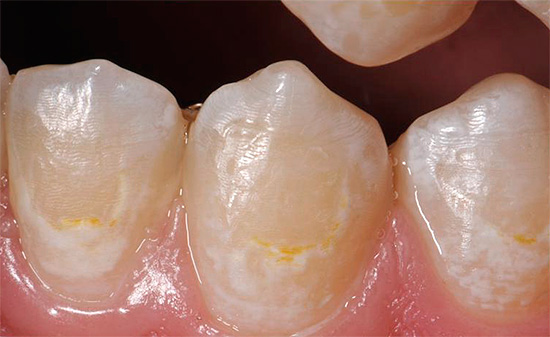

Nella maggior parte dei casi, il paziente non può riconoscere la carie dello smalto nelle prime fasi, poiché la clinica di questa patologia è scarsamente espressa. Quando appare un punto bianco o pigmentato, molti lo attribuiscono alla placca o al tartaro, non capendo la gravità del problema.

Il colore dello smalto interessato può essere diverso, a seconda delle caratteristiche del cibo assunto regolarmente e della presenza di alcuni coloranti in esso.

Nella foto sotto, la carie di smalto è presentata come la fase iniziale della lesione con segni caratteristici di questa particolare fase: